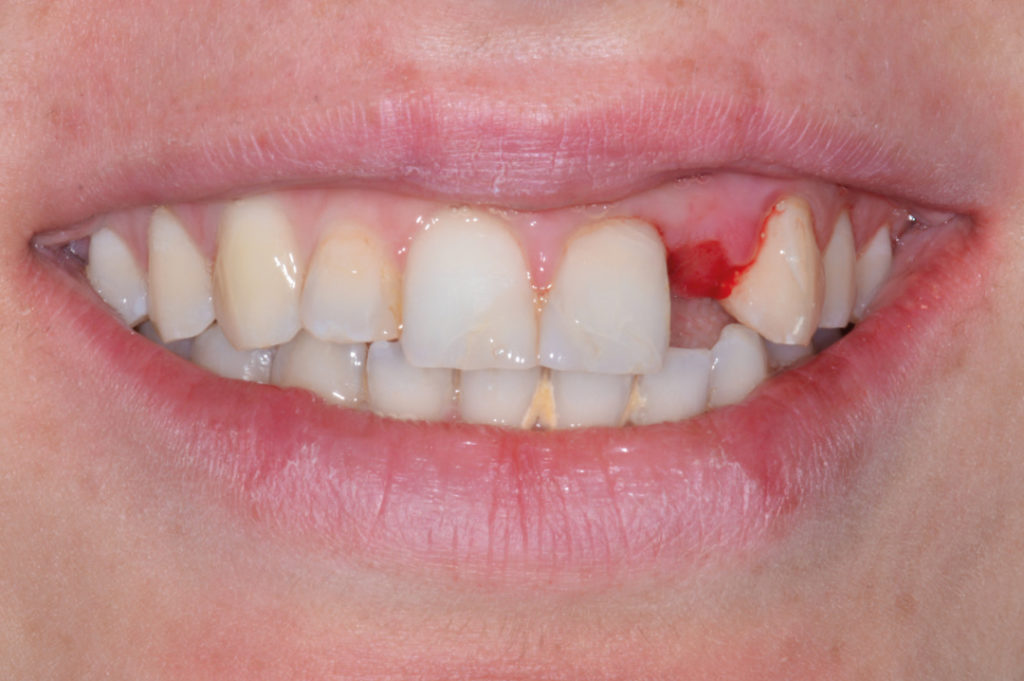

View of congenitally missing maxillary lateral incisor